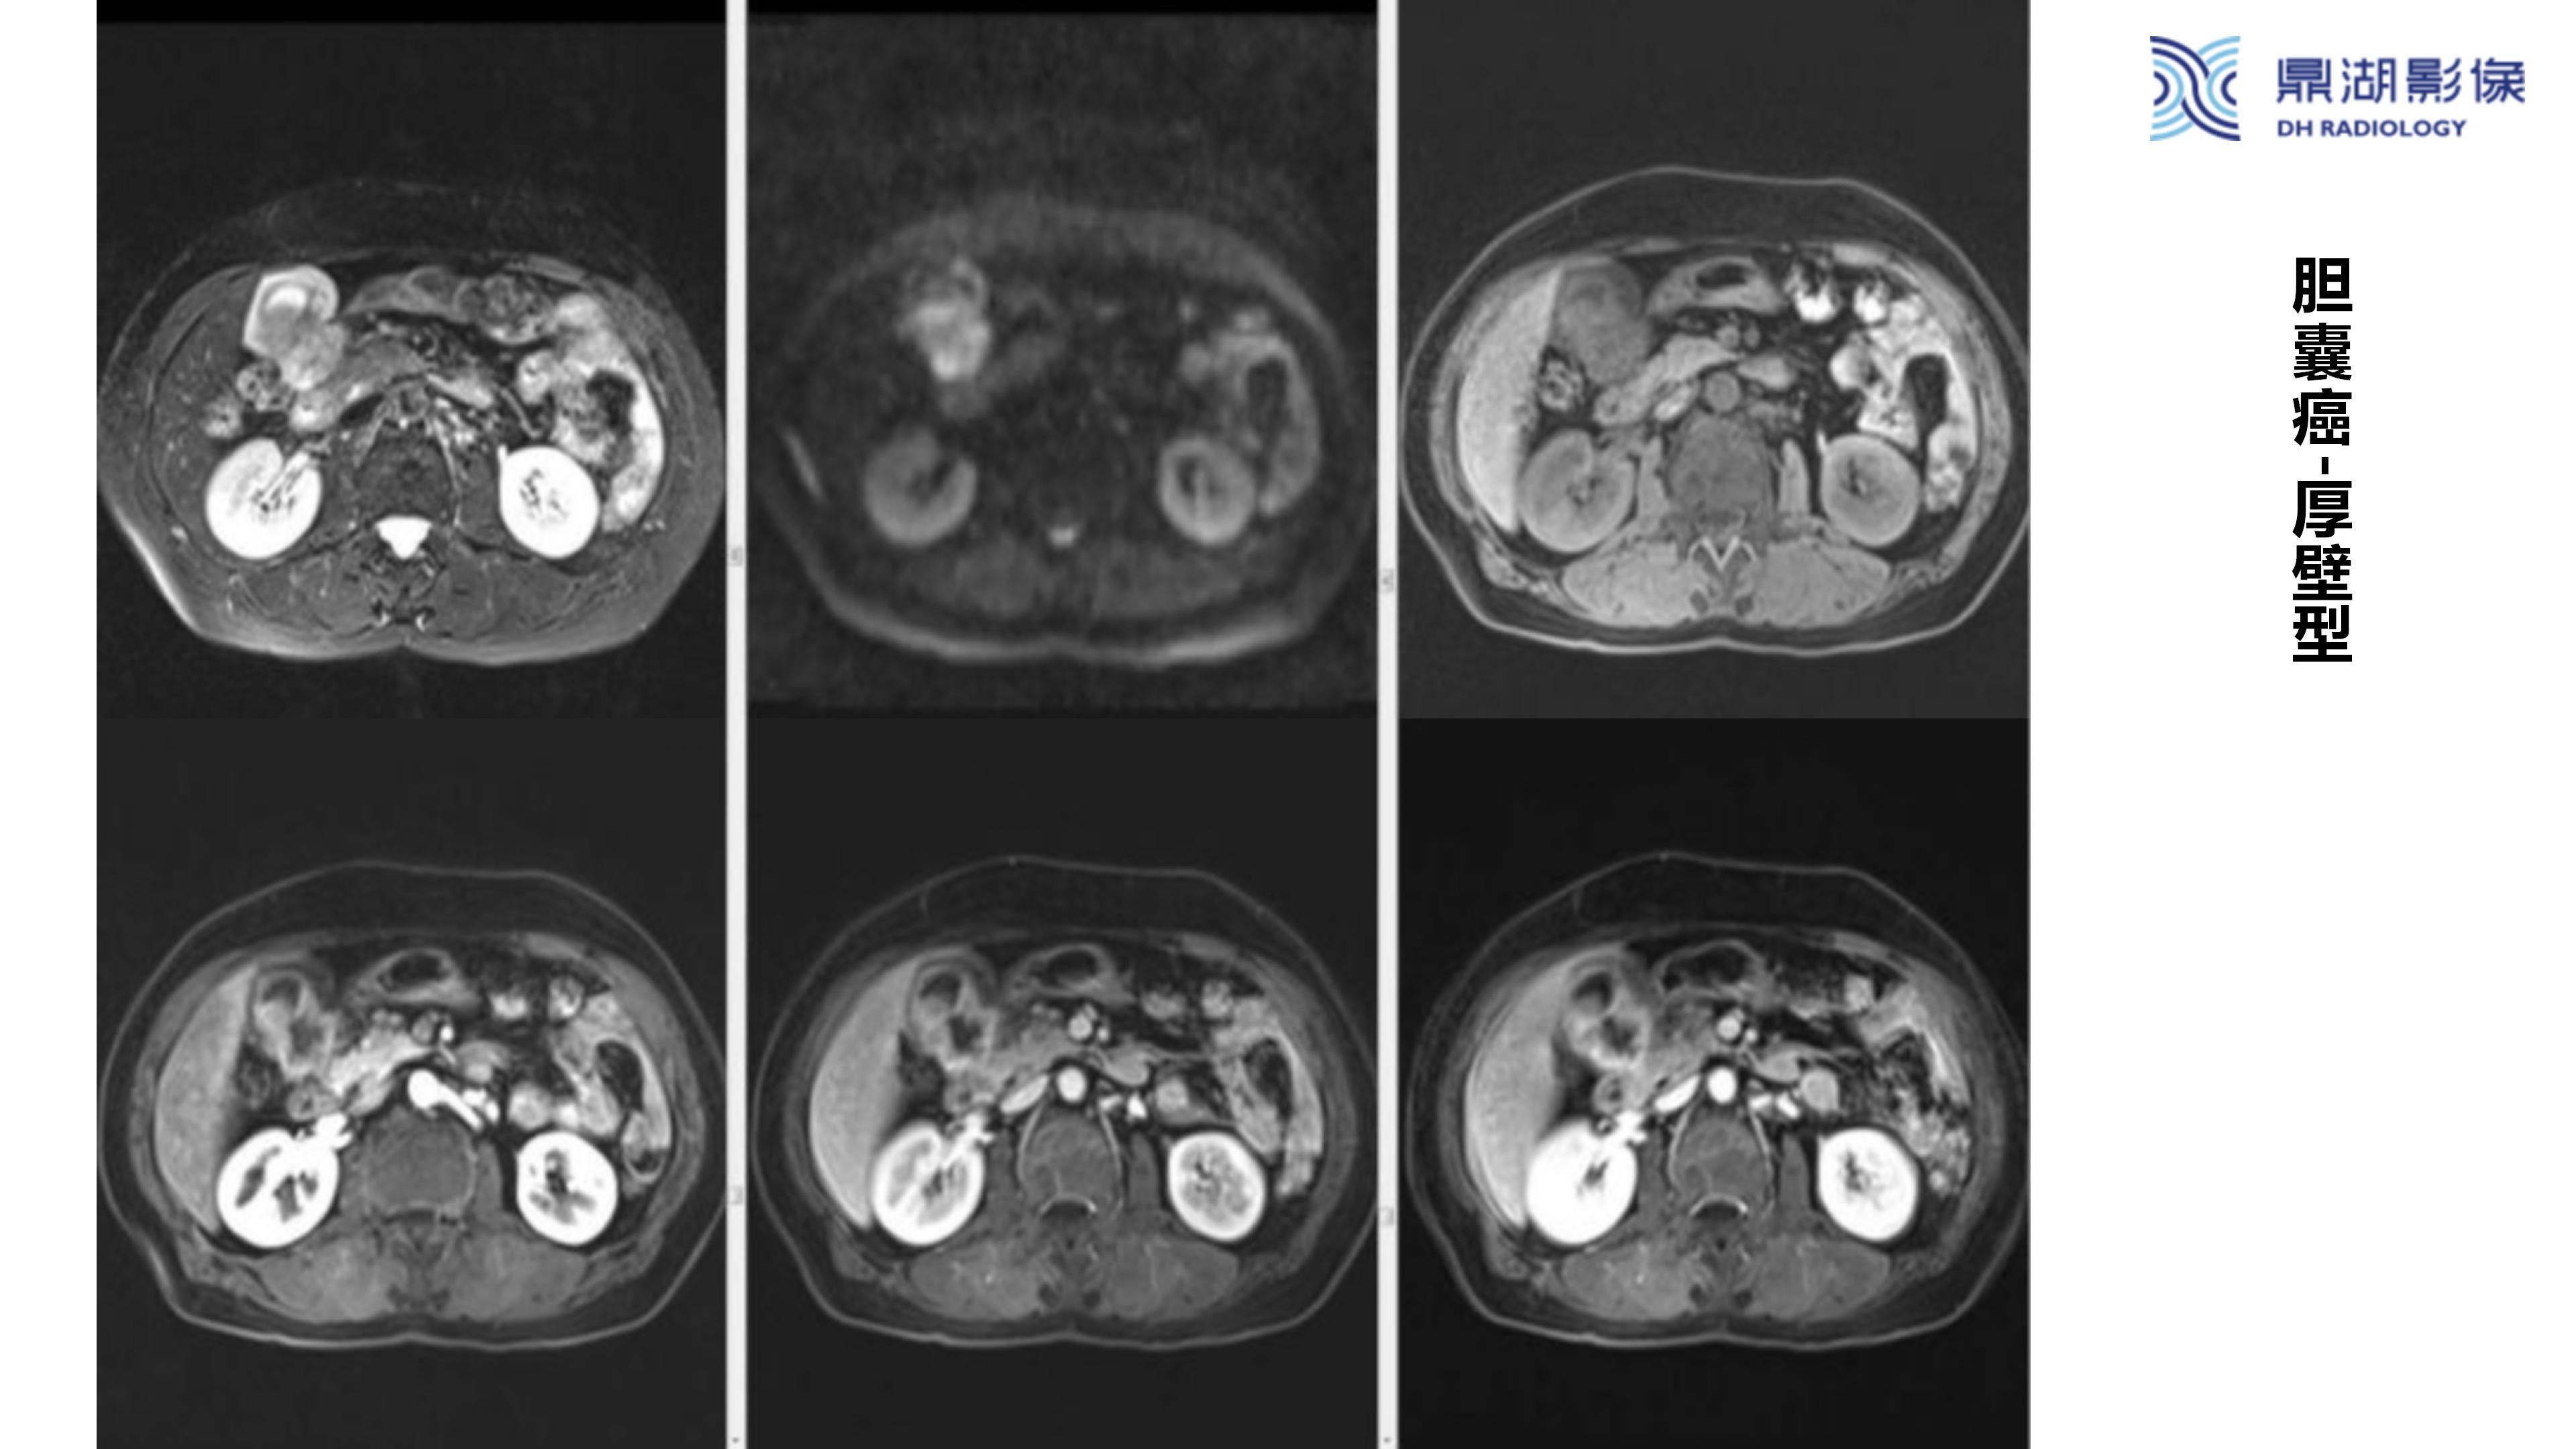

胆囊癌-鼎湖社群读片病例